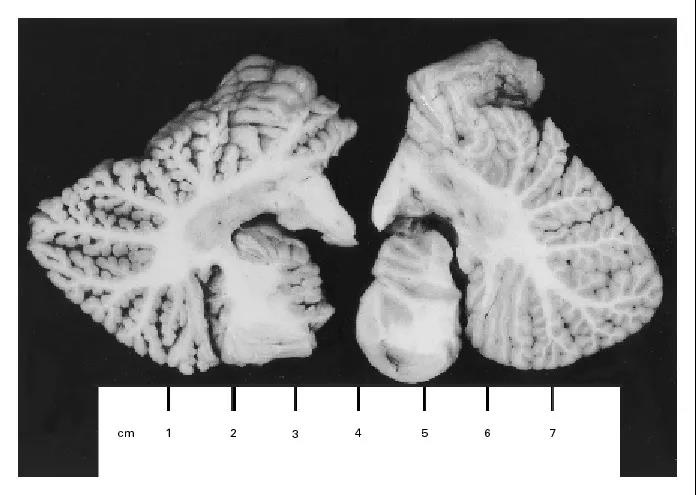

凯伦的大脑、尤其是额叶内聚集了大量有机汞,里面的神经元成片死亡——这种伤害是不可逆的。

凯伦(左)与正常人的小脑半球切片对比不久后,凯伦陷入了深度昏迷。